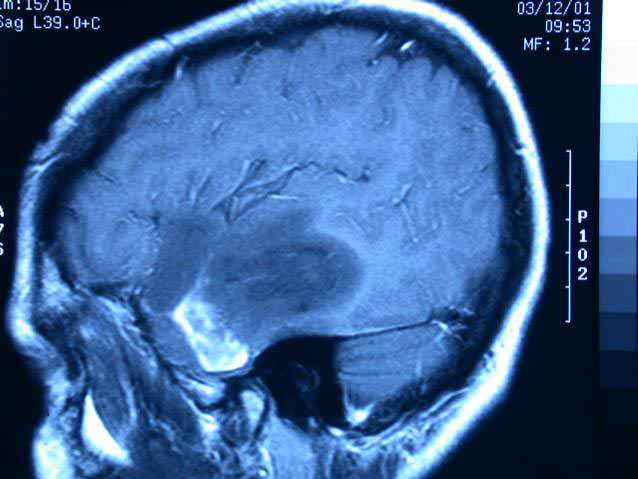

El glioblastoma multiforme es un tipo de tumor cerebral, un tipo de cáncer difícil de tratar; sólo pocos medicamentos están aprobados para tratarlo, y la expectativa de vida media para los pacientes diagnosticados con la enfermedad es de menos de 15 meses. Por tanto, los especialistas trabajan con una nueva nanopartícula liberadora de fármacos que podría ofrecer una mejor manera de tratar el glioblastoma.

En un comunicado del MIT, los científicos indicaron que las partículas, que transportan dos medicamentos diferentes, están diseñadas para que puedan atravesar fácilmente la barrera hematoencefálica y se unan directamente a las células tumorales.(Agencias)]